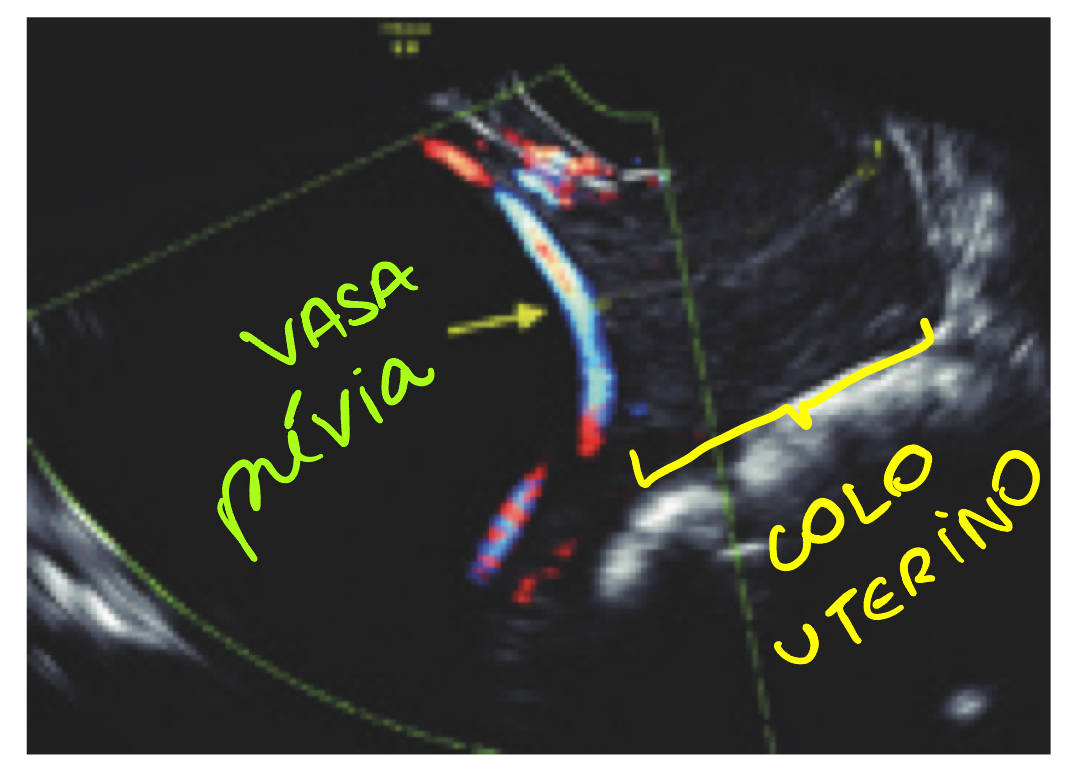

Como saber antes dos sinais clínicos que uma gestante apresenta vasa previa, e quais condutas adotar para assim evitar o seu rompimento?

A

USG TV com dopplefluxometria mostrando os vasos entre colo uterino e apresentação fetal

Conduta diante dessa USG:

- com 28-32s: iniciar corticoide (porque assim se romper, feto já esta preparado)

- 30-34s: internar, monitorizar

- cesárea eletiva com 34- 36 semanas